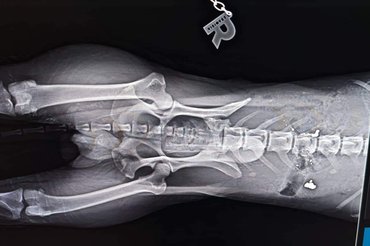

Az egyesület fogadta a sérültet, akit azonnal állatkórházba vittek. A vizsgálatok során kiderült, hogy a baj komolyabb, mint gondolták: a kutyát meglőtték, ráadásul többször is – tudtuk meg az egyesület egyik tagjától.

Abból, hogy valaki többször is rálőtt a szerencsétlen állatra, az egyesület egyértelműen szándékosságra következtet. Az eset súlyosságát csak tovább fokozza, hogy Emancs – így nevezték el a kutyust – gerince is sérült.

Mint megtudtuk, a gerincsérülés miatt kicsi az esély arra, hogy Emancs még valaha lábra álljon, ez pedig az altatás lehetőségét is felveti. Azonban az eszkuláposok úgy döntöttek, minden esélyt megadnak neki az életre.

Az esélyt viszont megkapja, mert neki is csak egy élete van. Ha a gerince rögzíthető, és túléli a beavatkozást, akkor kereskocsis kutyaként élhet tovább.